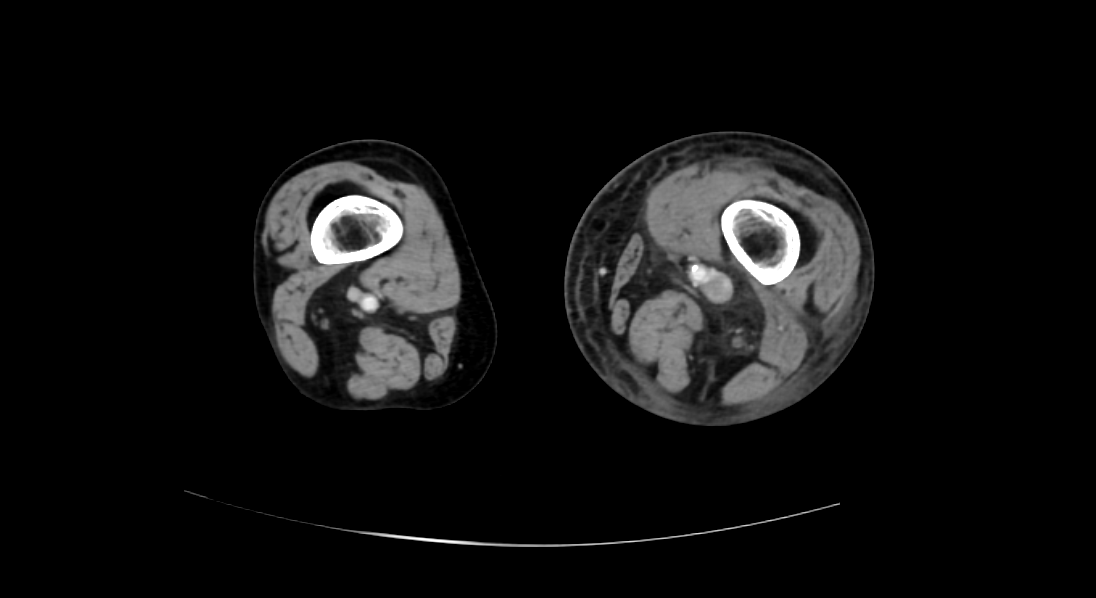

영상은 머리에 가까운 복부에서 다리 쪽으로 가는 순서로 나열하였다.

CT영상을 보면 좌측 장골정맥과 우측 장골동맥이 교차하는 지점에서부터 다리 말단 쪽으로 내려가며, 총장골정맥-외장골정맥-총대퇴정맥-표대대퇴정맥-오금정맥-경골정맥까지 혈전이 차있는 모습을 확인할 수 있었다.

Acute DVT, left CIV, EIV, IIV, CFV, SFV, popliteal and crural veins with compression of left CIV between vertebra and right CIA, c/w acute DVT with May Thurner syndrome.

Diffuse subcutaneous edema, left leg.